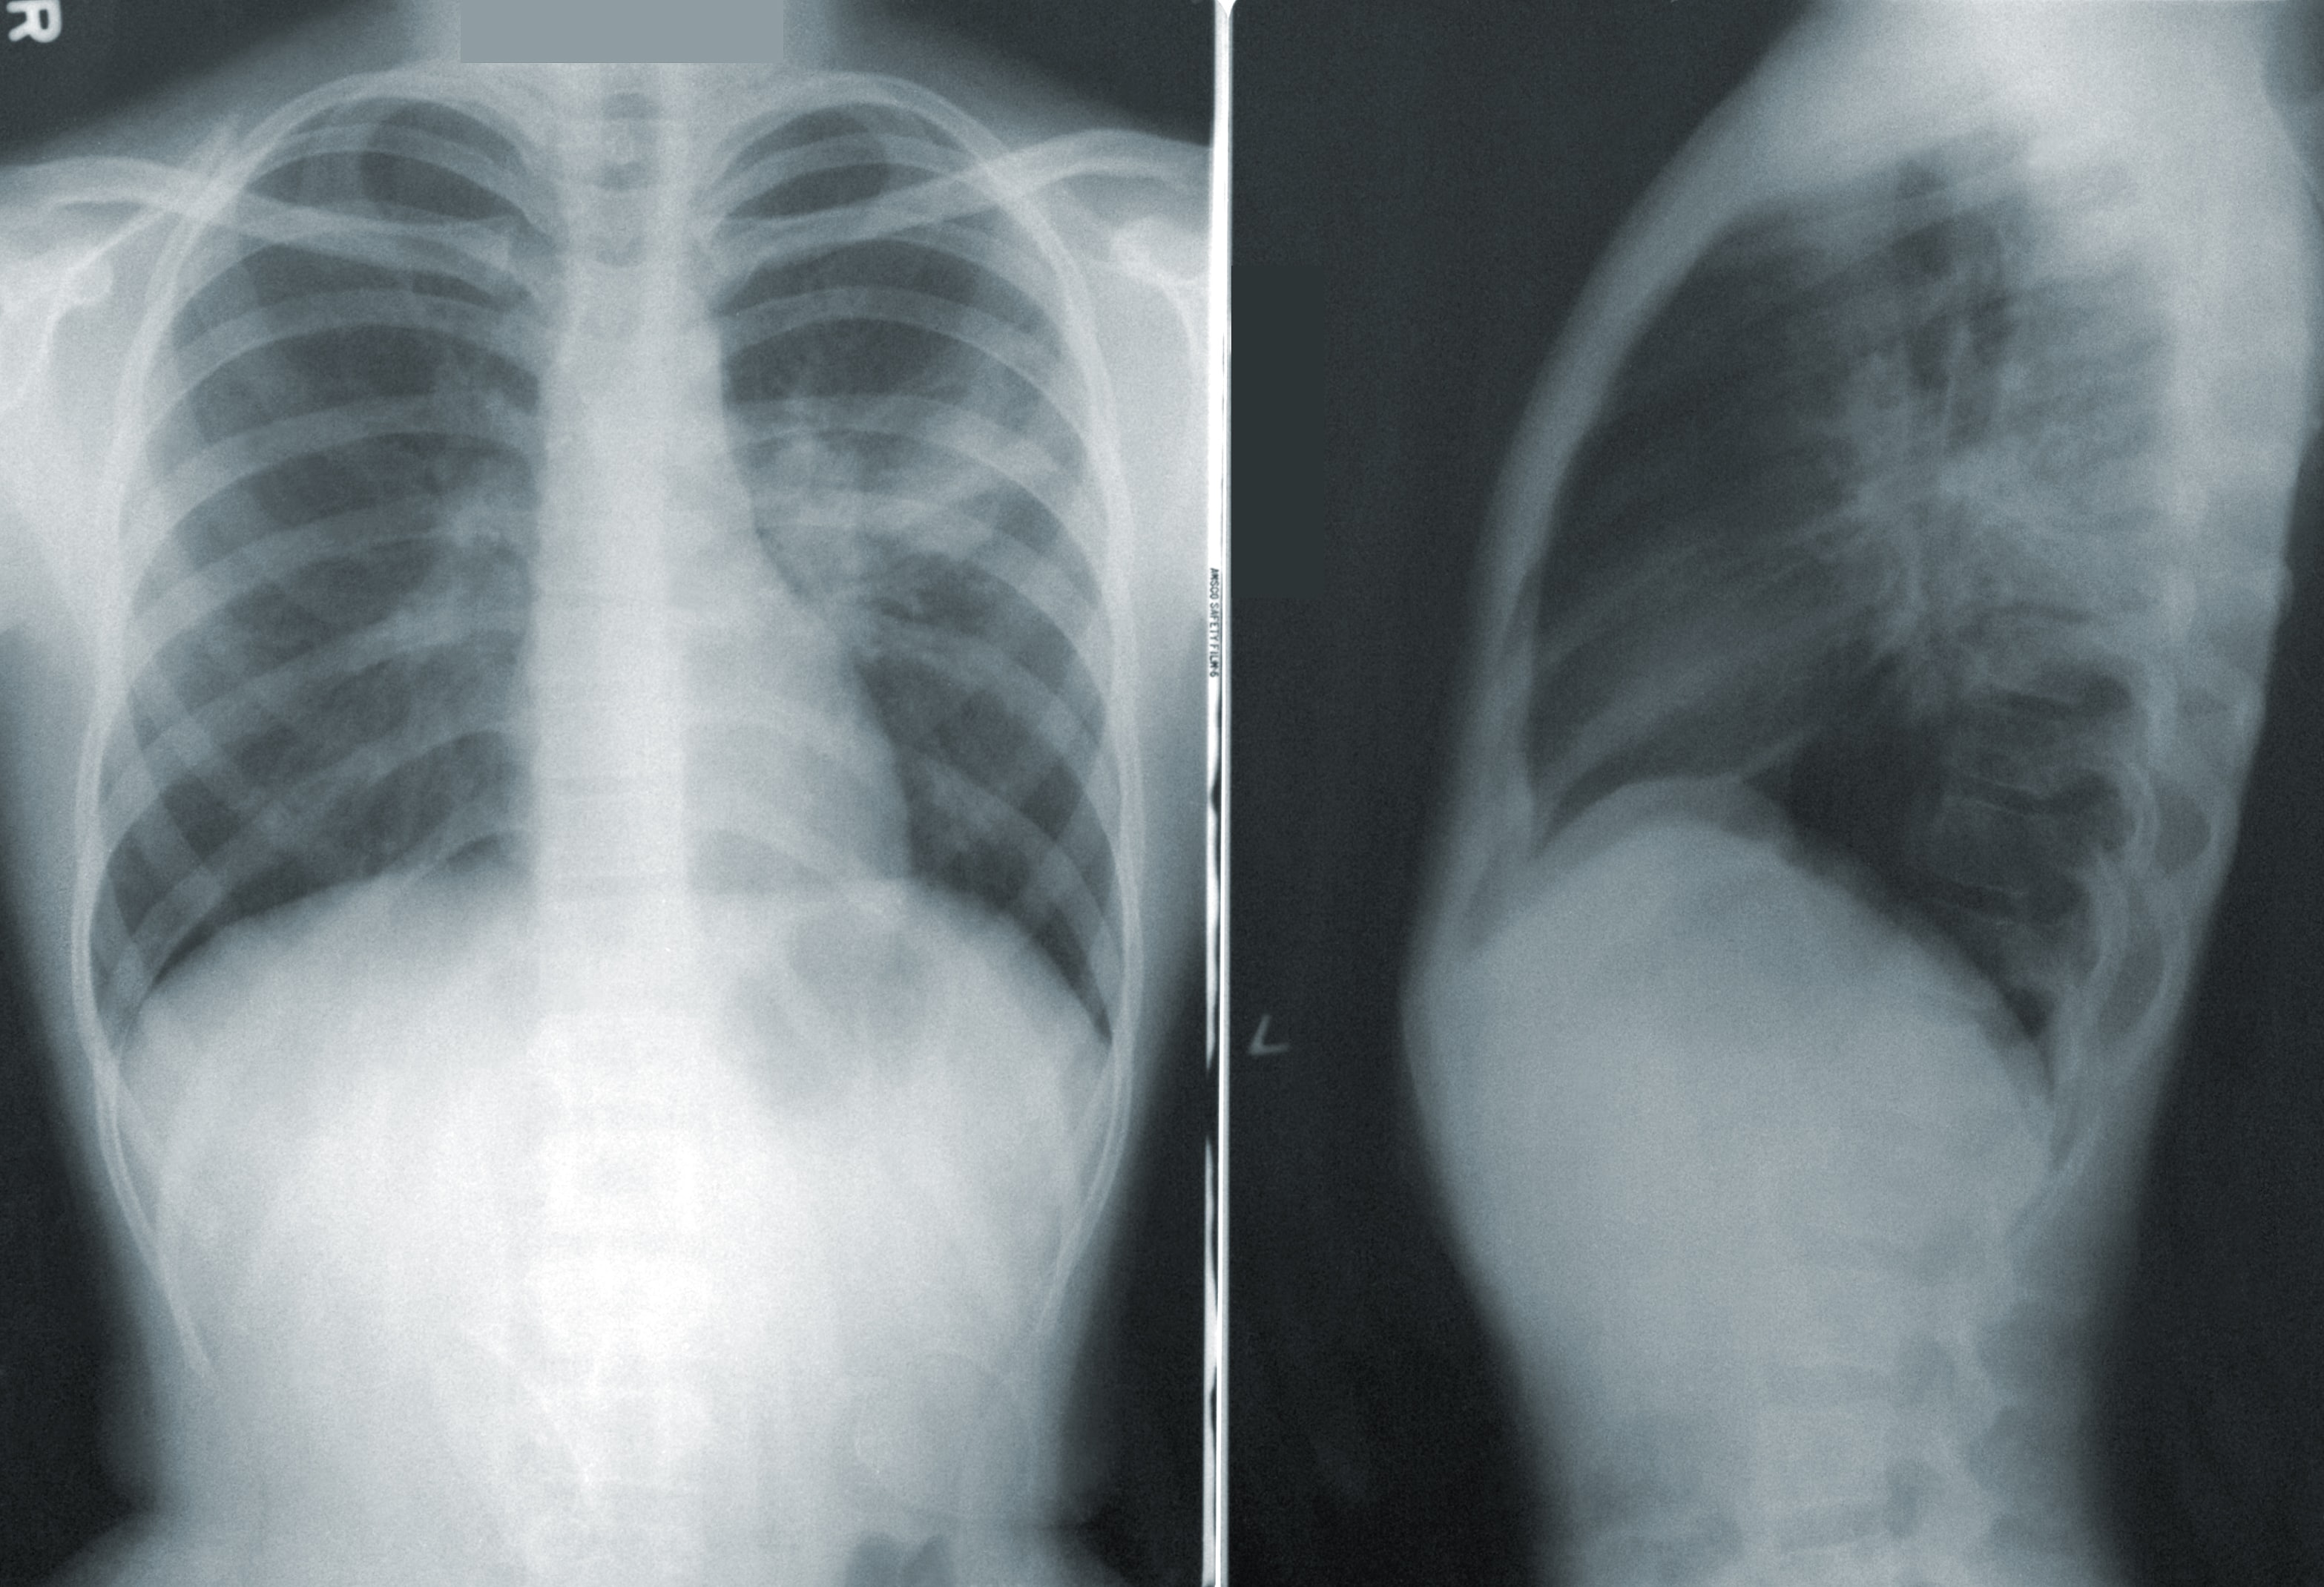

The most common detection method is Nucleic Acid Amplification Testing, in which a swab containing upper respiratory tract specimens is processed in a laboratory. However, processing variability can sometimes lead to delays. In such cases, and where patients already demonstrate respiratory symptoms of some severity, computed – or X-ray – tomography (CT) could assist in confirming infection. The images generated with CT technology can reveal the presence of a hazy ‘ground glass’ lung opacity which while not specific to COVID-19, is nonetheless common in patients and could thus indicate its presence.

Computed tomography, the gold standard in 3D X-ray imaging due to the detailed 360-degree images it generates, is a valuable tool for investigating illnesses and abnormalities affecting organs and blood vessels. For this reason, in addition to COVID-19 detection, it is also extremely useful for treatment response monitoring, and in the longer-term can help determine the nature and degree of any lasting impacts on organs. However, to construct a 3D image, scans take thousands of flat, 2D photos, which inject patients with a potentially harmful dose of ionising radiation.